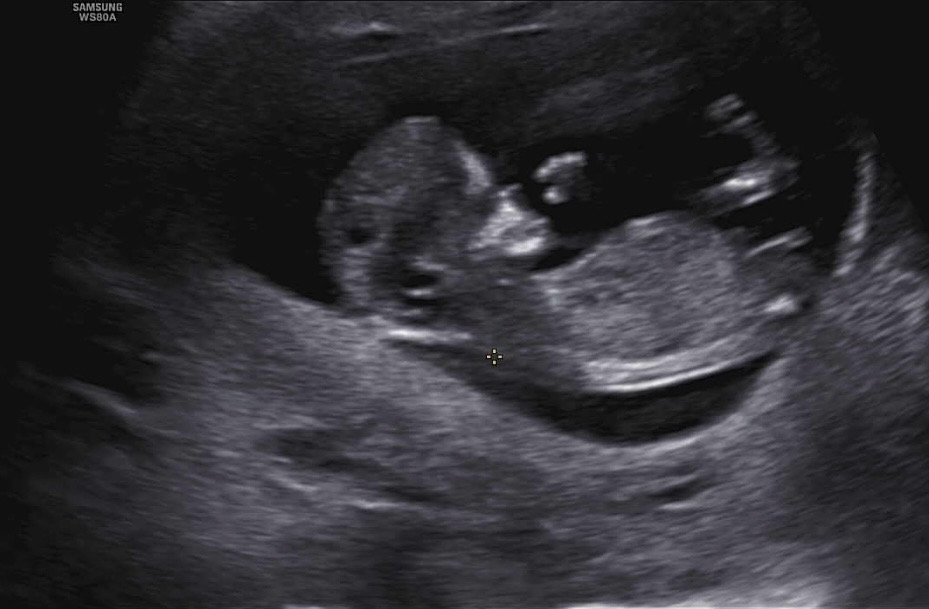

딱12주 사진이구 혹시 보이시는분 계실까요?? 너무 궁금한데 저는 잘 모르겠어서요ㅠㅠ

각도법 좀 봐주실분계신가요?ㅜㅜ